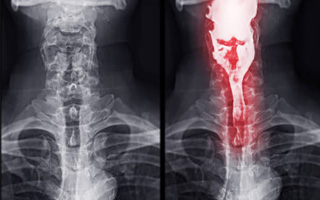

• Barium Studies: Barium tests are used to examine the digestive tract using a white powder called barium sulphate. This powder can be seen on x-rays. For a barium swallow or barium meal, the barium sulphate powder is mixed with water (and sometimes flavouring) then swallowed. X-rays are taken as you swallow the mixture.